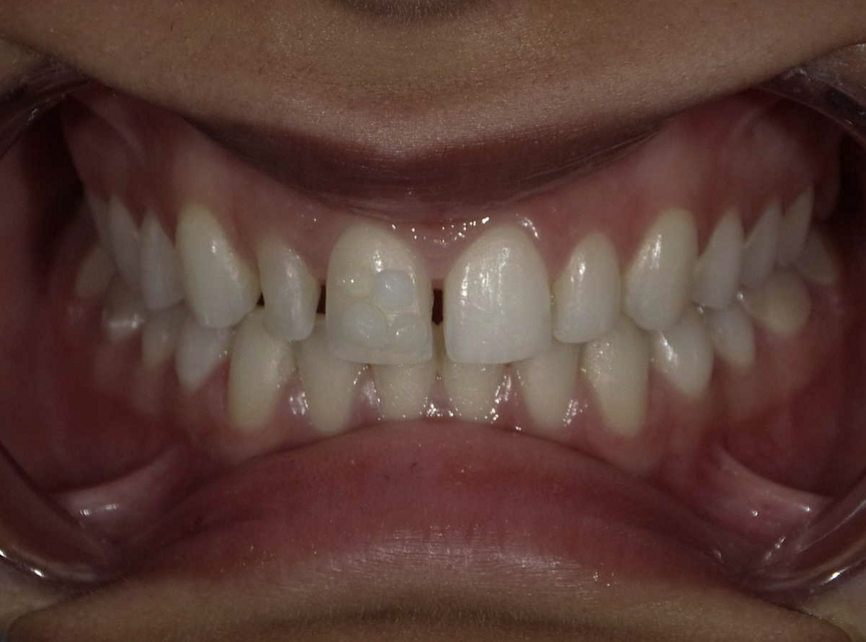

A young female patient visited the clinic requesting for an enhanced smile as she was unhappy with the appearance of her front teeth after completing orthodontic treatment. Upon careful examination it was observed that composite resin restorations were used for diastema closure before orthodontic treatment (Fig 1, 2). The filled teeth had chipped at the incisal edge and had a grey discolouration. After careful evaluation the following treatment options were suggested to the patient:

Fig 1: Pre-operative macro view of patient smile